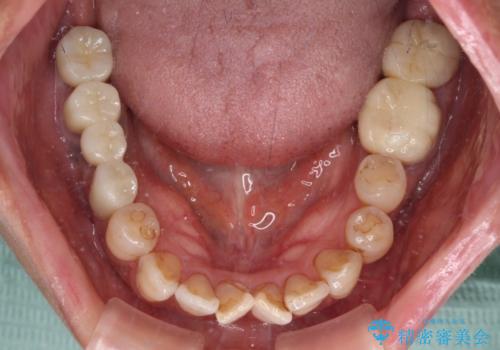

- 治療をおこなって以来、クラウン周りの歯肉から出血が続くとのことで来院された患者様です。

診察を行ったところ、クラウンと歯の境目が不適合で汚れが溜まりやすく、炎症を起こしている状態でした。

治療を終えたばかりですが、出血を改善するためには作り直しが必要と判断し、オールセラミッククラウンにて補綴治療することとしました。

仮歯に置き換えた時点で歯肉からの出血は収まり、不快感が改善されました。

右下は、残存歯の状態があまり良くなかったため、今後抜歯となったことを想定して、最後臼歯のインプラントを決定しました。